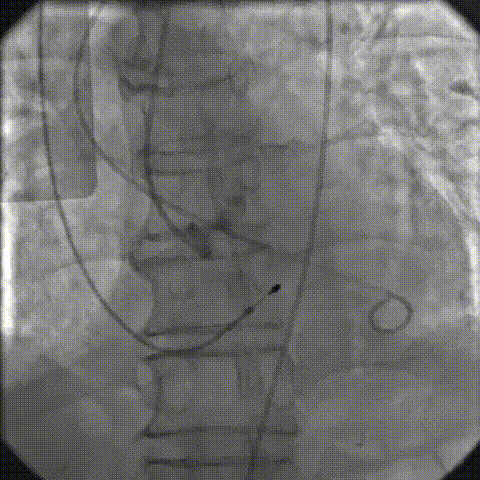

手术影像记录

主动脉根部造影

18mm球囊预扩

AV26瓣膜工作位造影

缓慢脱钩

23mm球囊后扩

后扩后造影:无漏

术中剪影